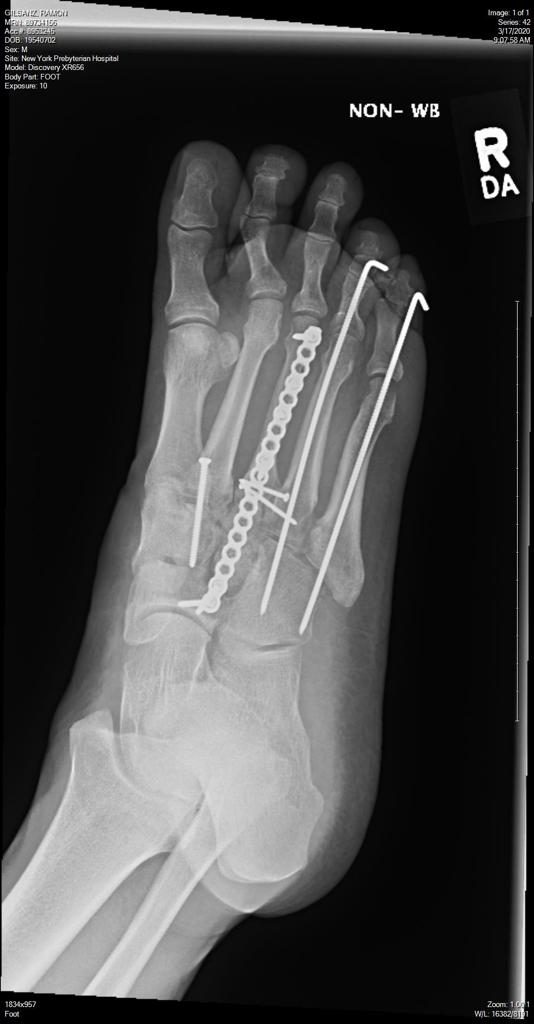

I hit a tree skiing in Colorado and suffered massive injuries to my right leg including breaking the femur, tibia, fibula and a level 6 Tibia Plateau Fracture. I was airlifted to Denver and placed in the ICU due to the extent of my injuries. After my femur was stabilized , I was flown to HSS  on a medical hospital jet and placed under the care of Dr. Helfet. Dr. Helfet, in multiple operations, rebuilt my right knee and my broken leg over the next 2 1/2 weeks. Upon my release from HSS I began physical therapy to rebuild my leg and regain my strength. 8 months after my accident I was able to ride a bicycle up the mountains on a 12.5 mile climb on a 30 mile ride.